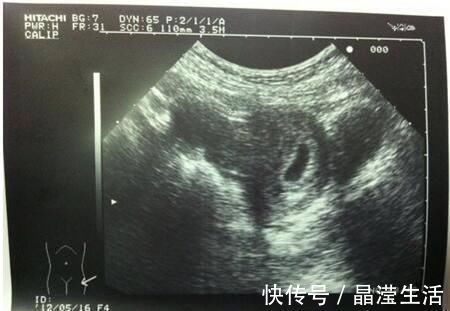

检查|怀孕两个月,检查没有胎心胎芽,检查只有个空壤这是什么情况啊?

你好很高兴能为你解答,希望能帮到你!如果平时月经周期规律,那么怀孕两个月还没有胚胎芽及心管搏动则多数提示胚胎停止发育,预后不好,不过临床上也不完全是这样,简要分析如下:

【 检查|怀孕两个月,检查没有胎心胎芽,检查只有个空壤这是什么情况啊?】2、如果既往月经规律,那么要结合超声及激素水平的情况来判断是否是胚胎发育异常,一般HCG3-5万即可见到胚芽心管搏动,孕囊达到2cm超过一周还没有见到心管搏动,则停育可能性大。